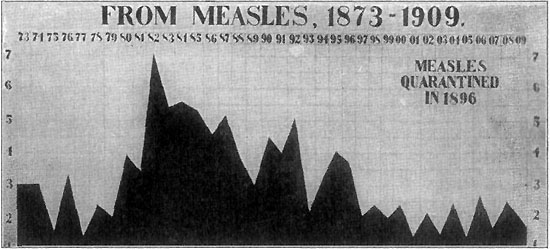

291 Death-Rate from Measles